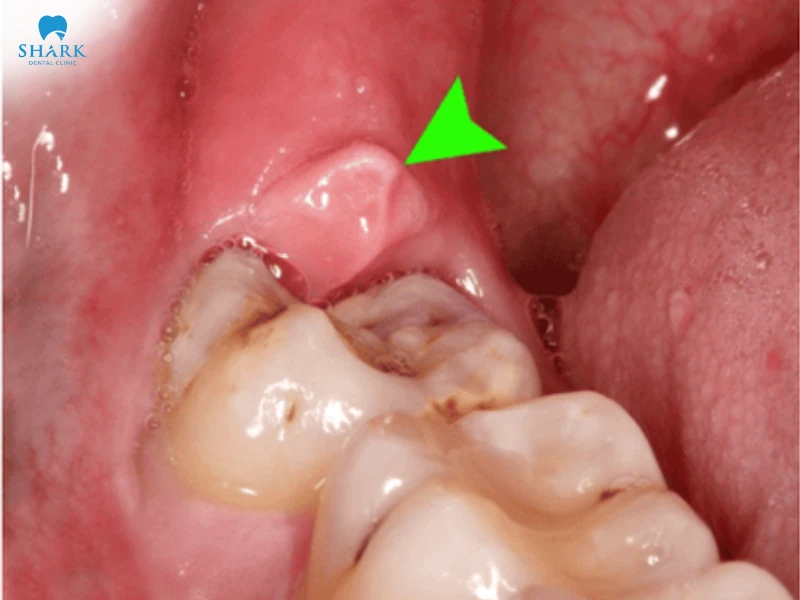

- Nướu sưng viêm: Vùng nướu quanh răng khôn sưng đỏ, căng tức và nhạy cảm hơn bình thường do răng đang đội nướu trồi lên. Tình trạng này thường kéo dài cho đến khi răng mọc ổn định.

- Sưng má: Khi răng khôn hàm dưới mọc lệch hoặc mọc ngầm, vùng má bên ngoài có thể sưng rõ, kèm cảm giác đau nhức và khó chịu khi chạm vào.